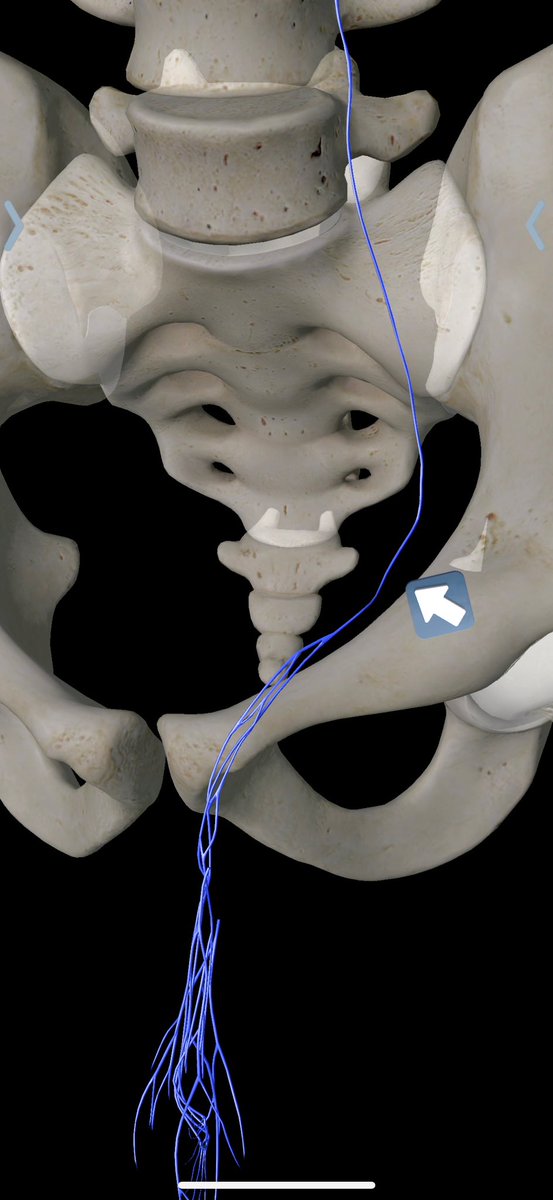

طريقة تغلغل الصمغ الطبي في علاج الأوردة المغذية لدوالي الخصية بالقسطرة. اغلاق جميع الأوردة بدون المساس بالقنوات الليمفاوية (فلا يحصل قيلة مائية) ولا الشعيرات الشريانية الدقيقة (فلا يحصل ضمور) القسطرة والأشعة التداخلية اثبتت بالابحاث افضليتها على الجراحة من كل النواحي

١٣- لاحظ ان خطر ربط الشرايين الفرعية (حتى وإن لم يؤدي الى موت الخصية) فانه قد يؤدي الى تضرر القنوات التي تنمو بها الحيوانات المنوية وقد يؤثر على الانجاب ولذلك "يفضل" المحافظة على الشريان وكل فروعه. بالصورة توضح شعيرات كثيرة يتم تمزيقها عند فصل الأغشية. بالمناسبة لا يوجد غشاء بجسم